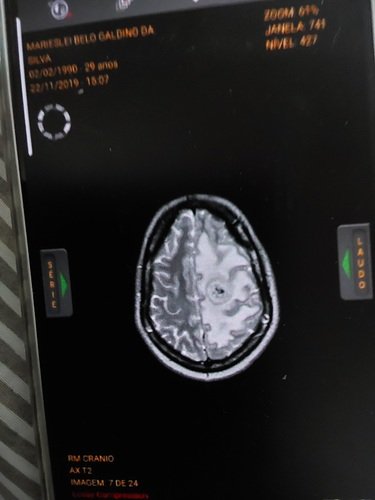

Oi eu sou a Mari tenho 33 anos em Agosto de 2017 fui diagnosticada com um tumor cerebral, fiz uma radio cirurgia, que não deu bom infelizmente, fez uma radio necrose.

Em 2019 tive 3 AVC, hoje perdi meu movimento de pinça, minha marcha não é mais a mesma, tenho encurtamento por conta da coluna.